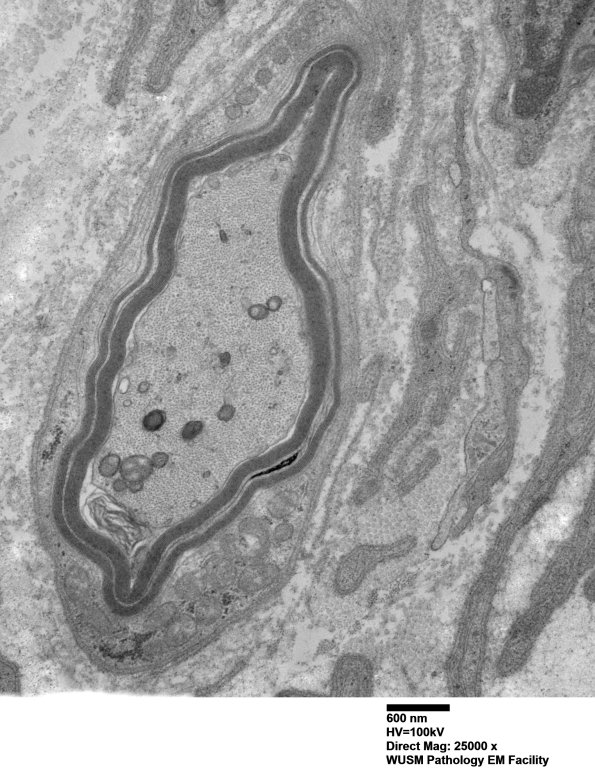

7C5A,B Again, notice the involvement of a Schmidt-Lanterman cleft. (electron micrographs)